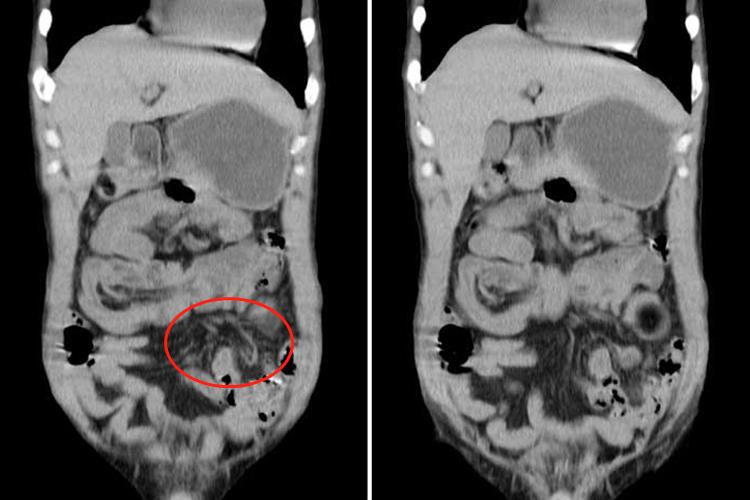

对于出现肠套叠的患者,CT检查常表现为腹腔内软组织肿块影,肿块呈高低密度相间的分层状或环状,分别代表套入部肠腔、肠壁、肠系膜脂肪及鞘部肠腔和肠壁,靶心为套入部的肠腔,其周高密度环为肠壁。增强扫描肠壁有明显强化。口服造影剂进入套入部,则靶心密度很高,CT表现以套入的肠系膜脂肪形成新月形或半环形的脂肪密度区最具有诊断特征。